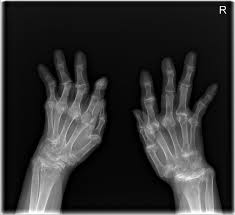

류마티스 관절염 진단 과정

류마티스 관절염의 진단은 여러 가지 방법으로 이루어집니다. 일반적으로 혈액 검사와 엑스레이, 염증 수치를 통해 진단을 받습니다. 혈액 내 류마티스 인자 및 항CCP 항체 검사로 류마티스 관절염을 확진할 수 있습니다. 진단 과정은 환자의 병력과 증상을 기반으로 하며, 전문의가 적절한 검사 방법을 선택하여 진행합니다. 이러한 진단 과정을 통해 류마티스 관절염인지 여부를 정확하게 판단할 수 있습니다.